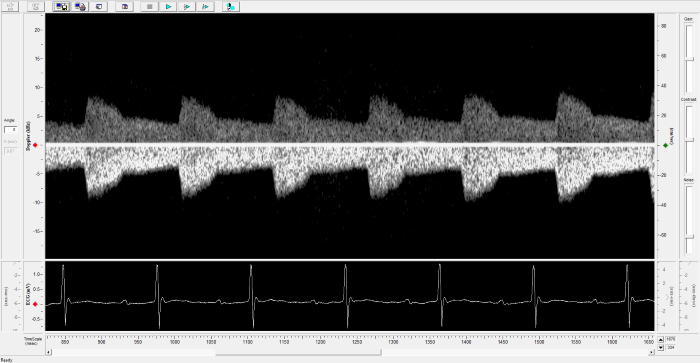

Imaging gallery - Doppler Flow Velocity System

Renal Flow. Image Credit: Scintica Instrumentation Inc.

Pulmonary Flow. Image Credit: Scintica Instrumentation Inc.

Mouse - Abdominal Aorta. Image Credit: Scintica Instrumentation Inc.

Mouse - TAC Procedure Imaging. Image Credit: Scintica Instrumentation Inc.

Rat - Left Carotid. Image Credit: Scintica Instrumentation Inc.

Rat - Transverse Aorta. Image Credit: Scintica Instrumentation Inc.

Rat - Right Carotid. Image Credit: Scintica Instrumentation Inc.

Rat - Abdominal Aorta. Image Credit: Scintica Instrumentation Inc.

Mouse - Left Carotid. Image Credit: Scintica Instrumentation Inc.

Mouse - Ascending Aorta. Image Credit: Scintica Instrumentation Inc.